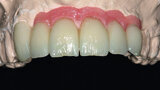

Fig. 38: Final cosmetic check-up showing correct lip support with the new extremely reduced false gingiva.

Fig. 39: Final cosmetic check-up showing correct lip support with the new extremely reduced false gingiva.